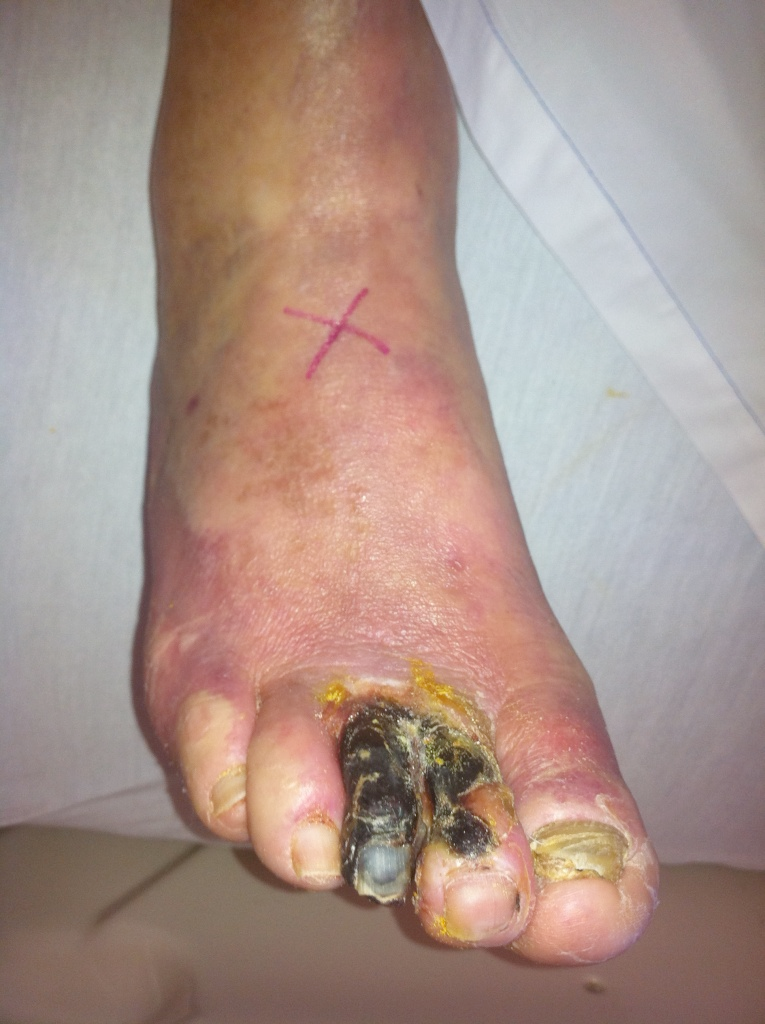

The clinical diagnoses for lumbar artificial disc replacement include symptomatic degenerative disc disease and post-discectomy syndrome. Post-discectomy syndrome is persistent back pain following previous surgery to remove a

herniated disc. For cervical artificial disc replacement, the diagnoses include cervical radiculopathy (where the nerve root is compressed) and cervical myelopathy (where the spinal cord is compressed).

Careful selection of patients for artificial disc replacement is critical. There are several conditions that may prevent patients from receiving a disc replacement. These include spondylolisthesis (the slipping of one vertebral body across a lower one), osteoporosis, vertebral body fracture, allergy to the materials in the device, spinal tumor, spinal infection, morbid obesity, significant changes of the facet joints (joints in the back portion of the spine), pregnancy, chronic steroid use or autoimmune problems. Also, total disc replacements are designed to be implanted from an anterior approach (through the abdomen for lumbar). Patients may be excluded from receiving an artificial disc if they previously had abdominal surgery or if the condition of the blood vessels in front of the spine increases the risk of significant injury during this type of spinal surgery.

In addition to the potential complications associated with general anesthesia, the complications associated with artificial disc replacement may include breakage of the metal plate, dislocation of the implant, infection, nerve injury and injury to blood vessels and urological structures. To help minimize complications associated with the implant itself, proper selection of patients and size of implant is very important. Also, artificial implants may fail over time due to wear of the materials and loosening of the implants.